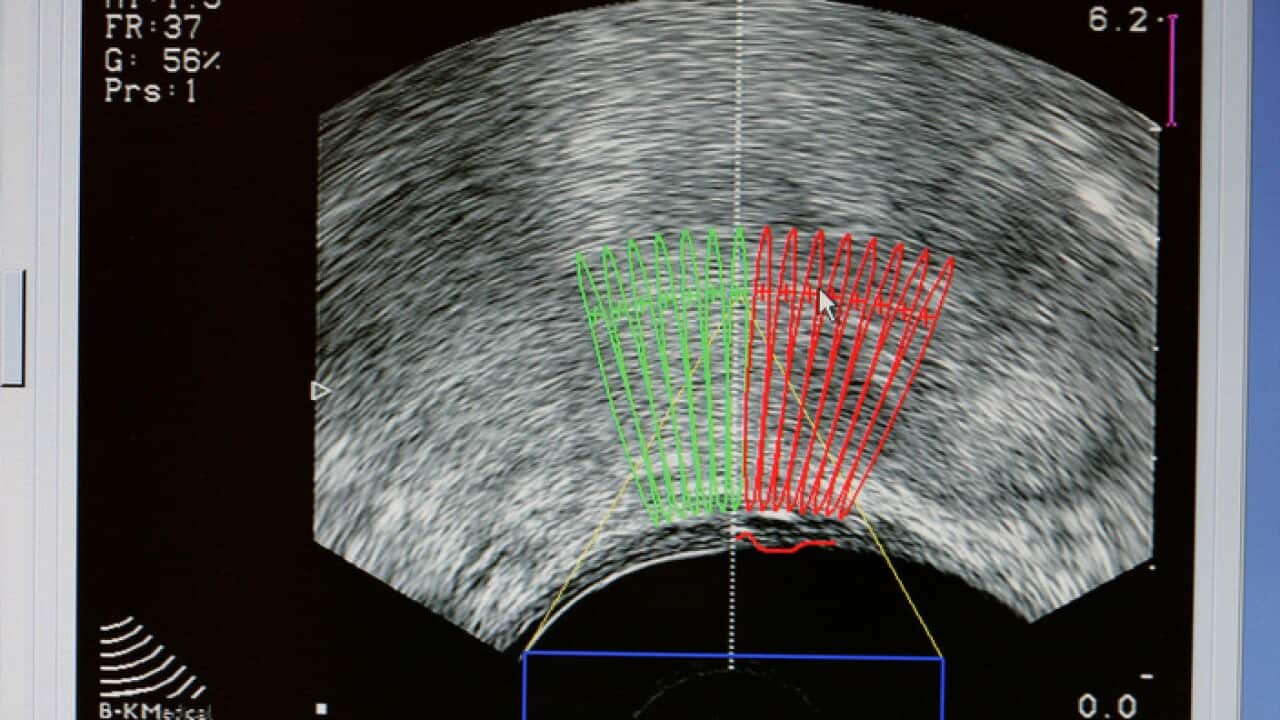

Prostate cancer ultrasound scan Source: Getty

Researchers discover prostate tumours can be starved of the fuel they need to thrive